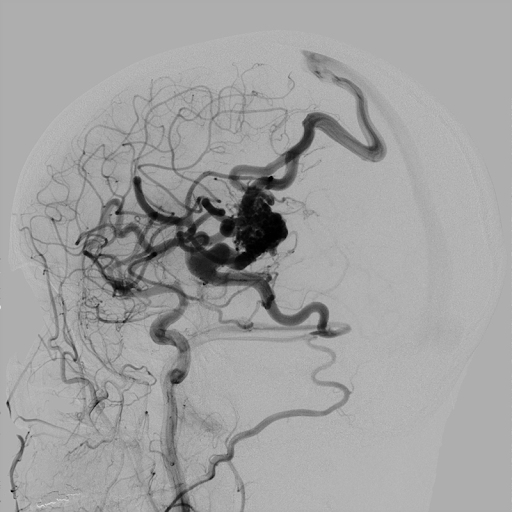

Передовые технологии визуализации для визуализации сердцa и коронарных сосудов:

- CV-3D™ plus

CV-3D – это функция трехмерного количественного анализа коронарных сосудов (3D QCA). Благодаря CV-3D проводится реконструкция 3D изображения сосудов из двух или трех ангиографических изображений, полученных при различных углах. На основе 3D изображения сосуды можно оценить длину, диаметр, наличие относительного стенозa и угол ветвления сосудов. Объемная визуализация коронарных артерий увеличивает детализацию изображения при чрезвычайно точных процедурах РСІ. Функиция "Stent Optimizer" улучшает визуализацию стента, за счет подавления фоновых анатомических структур и фонового шума на одном изображении, в то время как баллон находится еще в просвете сосуда после раскрытия стента.

- Multi modality Roadmap

Toshiba предлагает новую функцию Roadmap, позволяющая наложить 3D изображения с КТ на "живое" изображение флюороскопии. Такое совмещенное изображение помогает интуитивно понять позицию катетера, упрощая процесс его установки.

- CAAS A-Valve

Данная технология позволяет проводить анализ корня аорты за счет ее трехмерной реконструкции на основе двух ангиографических проекции.